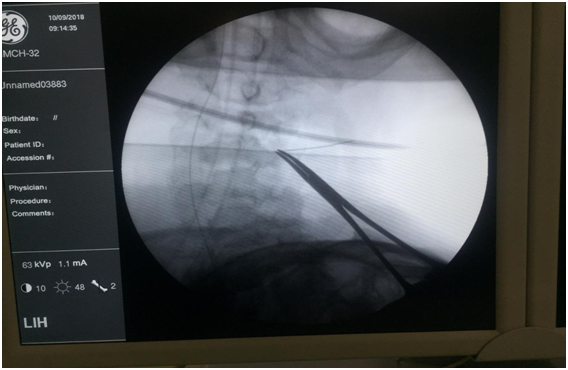

So, decision was made for surgical exploration via transcervical approach. Patient was positioned with neck extended with face turned towards opposite side (left side). Incision was made two finger breadths below the angle of mandible. After raising subplatysmal flaps, the ipsilateral strap muscles were retracted medially and sternocleidomastoid was retracted laterally. After identifying trachea and esophagus medially and major vessels laterally, dissection was carried out in paracarotid region. Prevertebral fascia was dissected and no foreign body was seen. C-arm was used to localize the foreign body and edge of the foreign body (needle) was visualized with the help of C- arm Figures 3 & 4. Needle was removed after grasping with forceps. Negative suction drain no. 14 was put and fixed. Wound was closed in 2 layers. Immediate post-operative period was uneventful. Nasogastric tube removal and drain removal were done on post-operative day 3. On post-operative day 7, complete suture removal was done. Patient was discharged in stable condition after suture removal. Patient was prescribed oral antibiotic (Tab. Amoxyclav 625 mg TDS for 7 days), C. omez 20 mg OD and Tab. voveran 50 mg sos. Patient was followed up after 7 days and was normal with no fresh complaints. Neck wound was healthy.

Figure 3 Foreign body localization with the help of C-ARM.

Figure 4 Intraoperative localization of foreign body showing head of the foreign body with part of it inside the subcutaneous tissue (blue arrow).